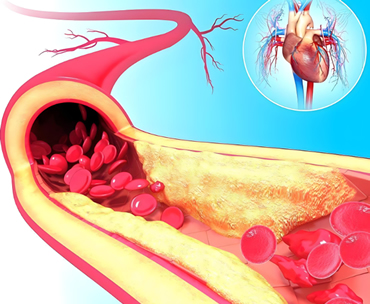

事实上,无论是长度还是体积,毛细血管都占到了整个心血管系统的绝大部分比重。如果所有的毛细血管开放,可以达到20L的容积,而血液的总容量,也就4~5L。

传递的广度,决定了传递的数量。正因为毛细血管的庞大,它才有能力服务每一个细胞的新陈代谢,给它们输送氧气,提供养分,带走它们的代谢产物。所以,毛细血管的广度,造就了心血管系统对身体37.2万亿细胞的影响力。

心血管决定了各个脏器的供血,给谁多一点,分谁少一些,甚至在最紧急的关头,心血管有权选择依次放弃哪些器官,哪些组织,保证谁的供应。

更为厉害的是,在往下输出的每一层过程中,心脏射出的血液成分直到营养细胞前没有任何改变,也就是达到价值100%的传递,几乎是0损耗。做到了层递的高度通畅,也就完成了价值的有效输出,继而成就心血管的影响力。